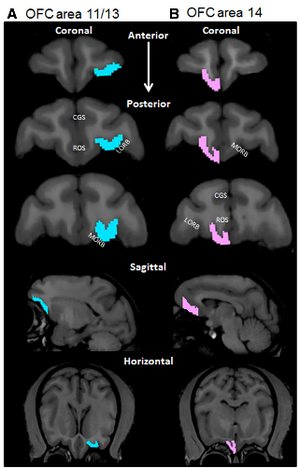

- 4.20 Orbitofrontal Cortex Volume in Area 11/13 Predicts Reward Devaluation, but not Reversal Learning Performance, in Young and Aged Monkeys

- 4.21 Robust Radiomics Feature Quantification using Semiautomatic Volumetric Segmentation